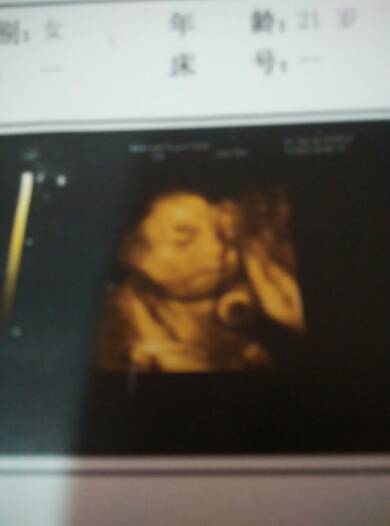

我家男宝宝有趣吧…看看就开心好笑 我家男宝宝有趣吧…看看就开心好笑 点击展开 我爱ぜ我喜欢ж你 2015-05-27 13:36 为您推荐: 其他回答 可爱。。s 晴空下的向日葵s 2015-05-27 16:00 祝宝妈好孕 你的一切都是我的! 2015-05-27 14:34 祝宝妈好孕 宝贝,我爱你!n 2015-05-27 14:21 恭喜宝妈好孕 泡沫_rHSS 2015-05-27 14:04 祝宝妈好孕哦 ﹎﹎Venus╮唯爱、 2015-05-27 13:58 加载更多 相关问题 在QQ上怎么都一个女孩开心,给他笑话他说不好笑,要怎么办 我宝宝也最喜欢爬了,看他爬我觉得很有趣,他也开心 我宝宝也最喜欢爬了,看他爬我觉得很有趣,他也开心